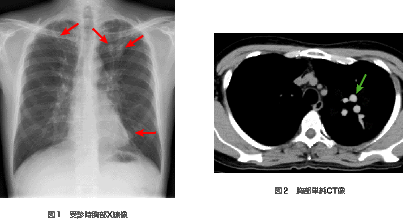

1748ページ 図1,図2(2009/3/6)

※画像中に矢印が欠落しておりました